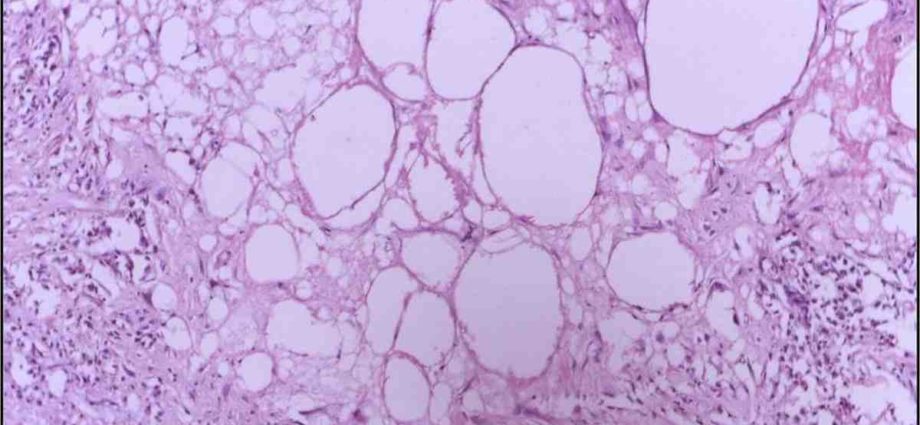

Pratiquement tous les organes, tous les tissus et toutes les cellules sont soumis à ce renouvellement cellulaire permanent et vont être complètement régénérés plusieurs fois dans une vie, à une fréquence plus ou moins élevée en fonction des cellules. Ce qui fait qu’au bout du compte, l’immense majorité des cellules et des organes sont plus jeunes que l’individu lui-même.

Ce vaste écosystème cellulaire – qui est finalement notre organisme – contient environ 250 types de cellules différentes. La grande majorité est soumise au renouvellement cellulaire, sauf quelques exceptions, comme, par exemple, les neurones et les cellules cardiaques où le renouvellement est très lent ou quasi inexistant.